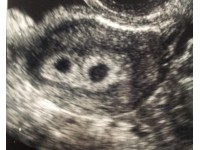

HOW TO DETECT PREGNANCY IN DAIRY CATTLE

The establishment and subsequent success of pregnancy can be vital for the livelihood of the farmers that rely on breeding their animals.

The use of veterinary ultrasound in pregnancy detection has been well documented in previous years, and is now considered to be a routine procedure when attempting to establish pregnancy/elucidate the current stage of gestation. However, it is important to carefully consider the type of ultrasound scanner that is used and to ensure it is the correct device for the task in hand.